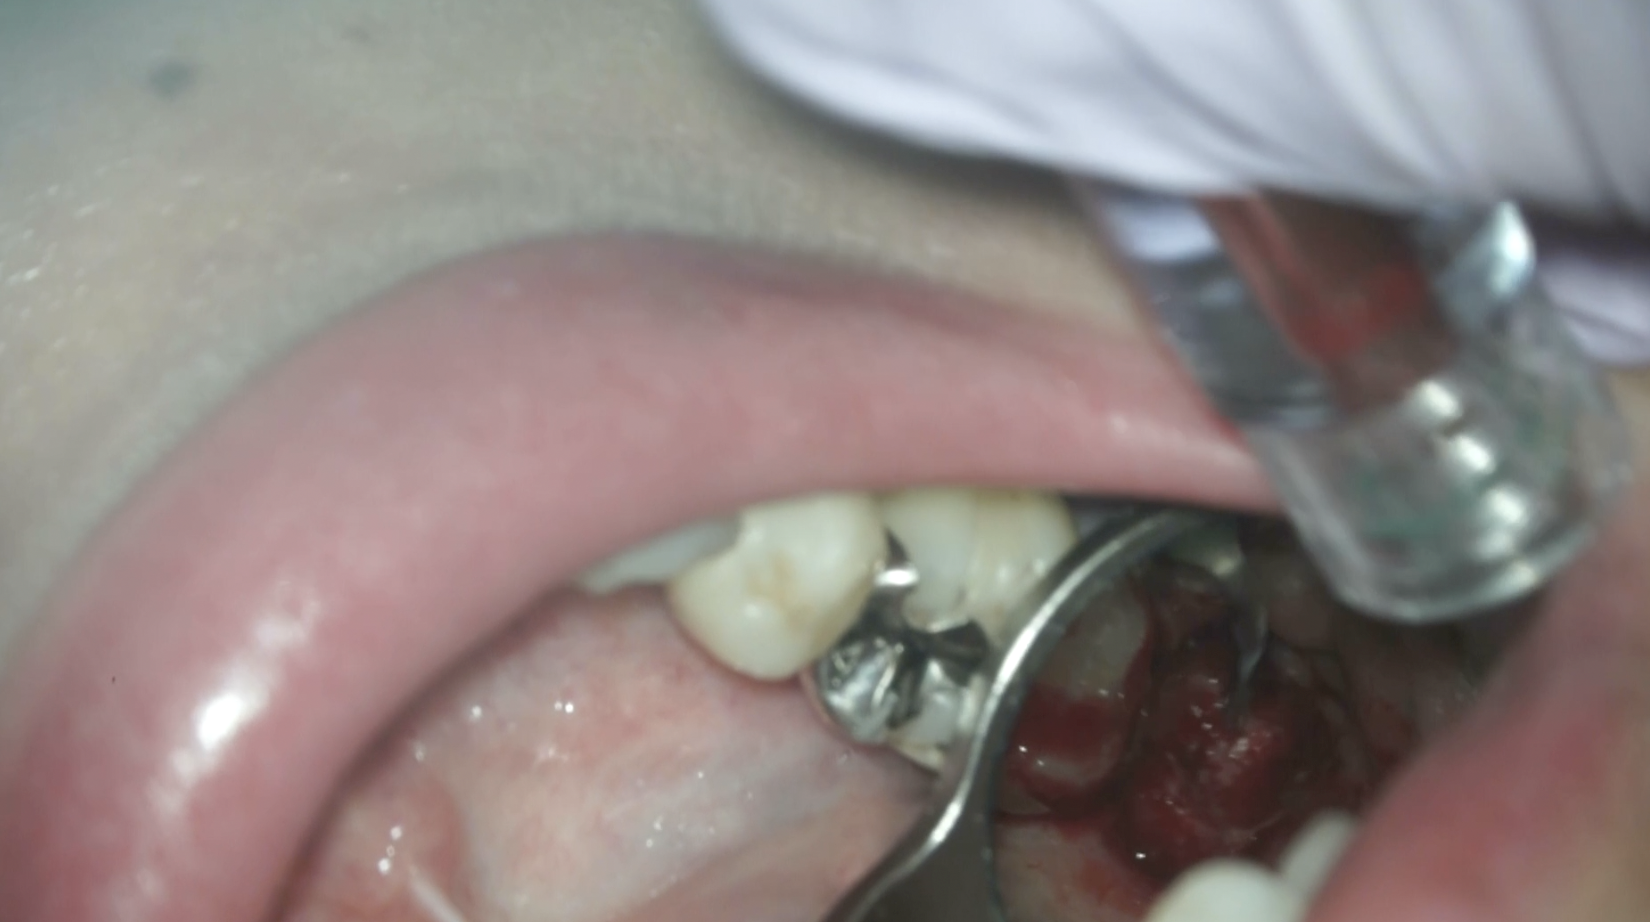

#2 Intentional Replantation(2025.12.12)

脱臼して抜歯しているので再植は難しいであろう…という印象を抱かさせるような抜歯作業だ。

抜歯窩を確認した。

ここからは口腔外作業になる。